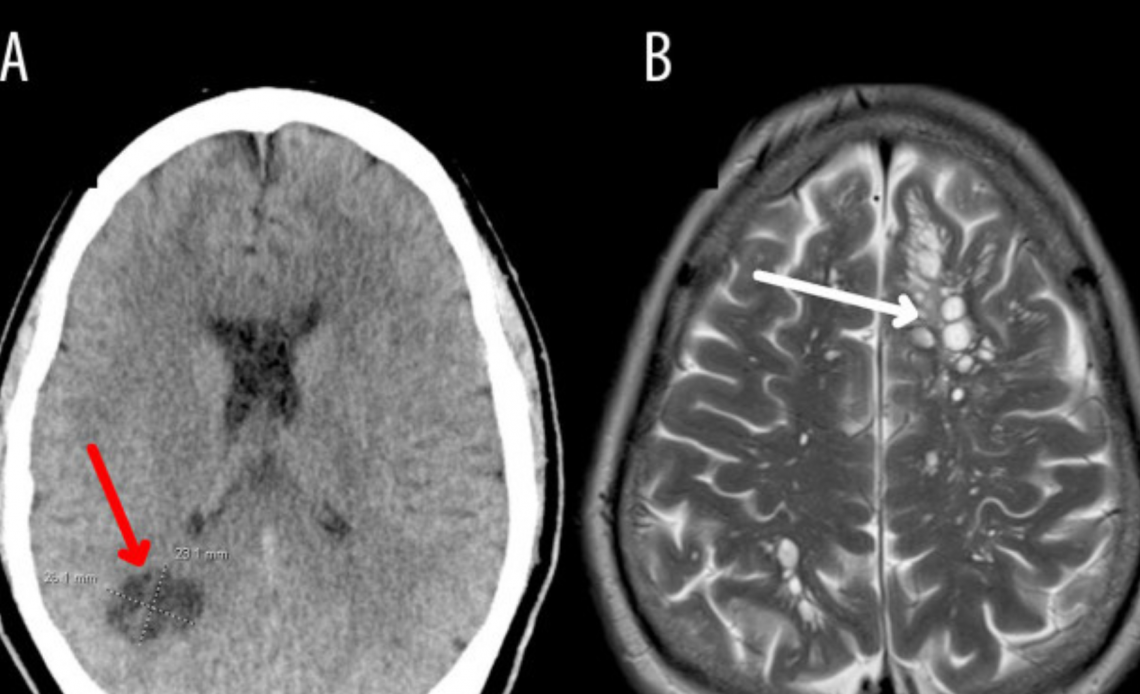

Los médicos especularon que las intensas migrañas, que no respondían a los medicamentos convencionales, podrían estar relacionadas con el consumo de tocino crudo por parte del paciente. Tras realizar una tomografía, se detectaron múltiples quistes en todo el cerebro, lo que llevó al ingreso del paciente a un hospital en Orlando para exámenes más detallados.

Los análisis revelaron que los quistes eran larvas de tenia parasitaria, causando una infección conocida como neurocisticercosis. Esta infección se produce cuando una persona ingiere huevos de tenia procedentes de las heces de un individuo con tenia intestinal.

El tratamiento incluyó esteroides y agentes antiparasitarios, lo que ayudó a aliviar los síntomas del paciente y reducir los quistes cerebrales. Este caso subraya la importancia de la preparación adecuada de los alimentos y la higiene personal para prevenir enfermedades parasitarias.